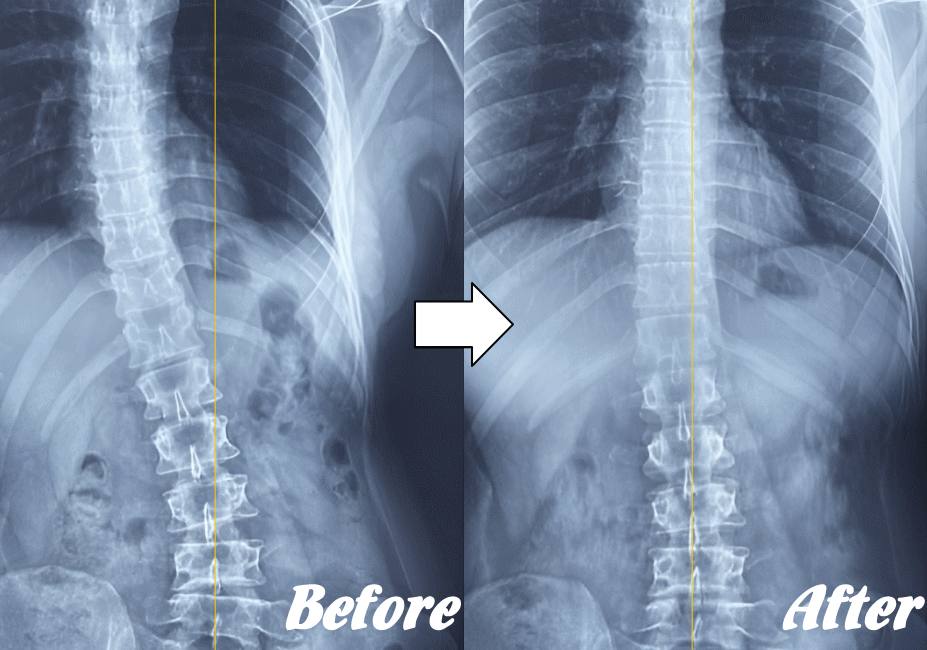

【体の整体】による変化

※ X線/MRI/CT検査画像のデータをお持ちの方はご持参いただければ当院で参考にさせていただきます。

施術前と施術後01